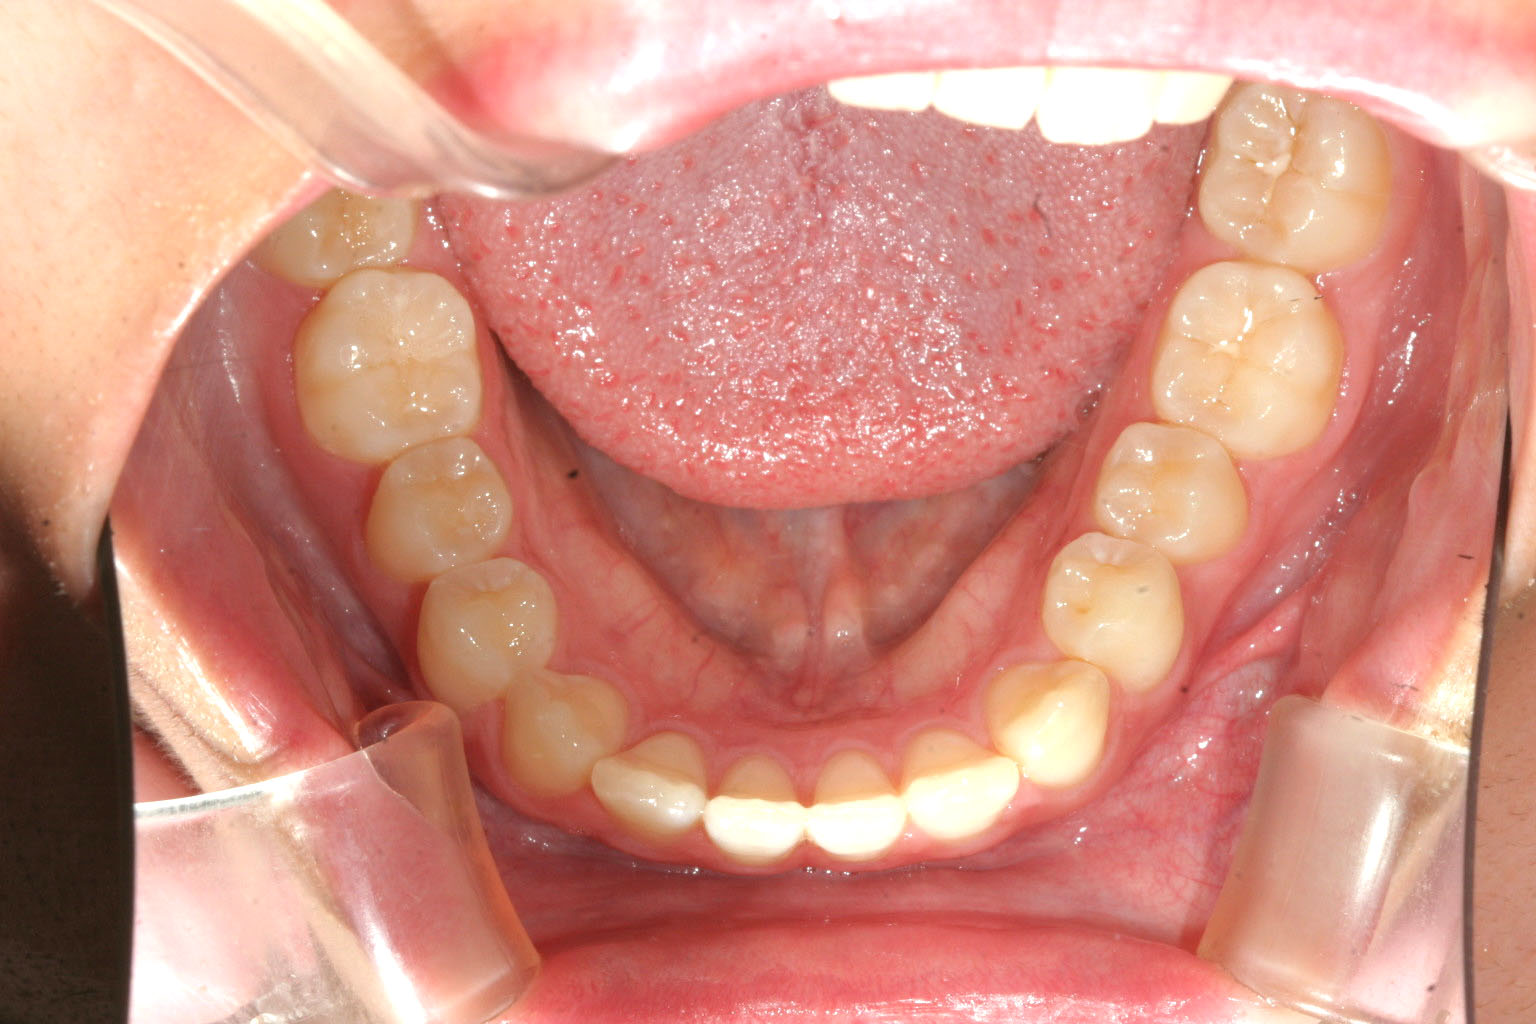

下顎の歯は綺麗に並んでいます。

下顎は元から綺麗だったのであまり触るとこが無いです。